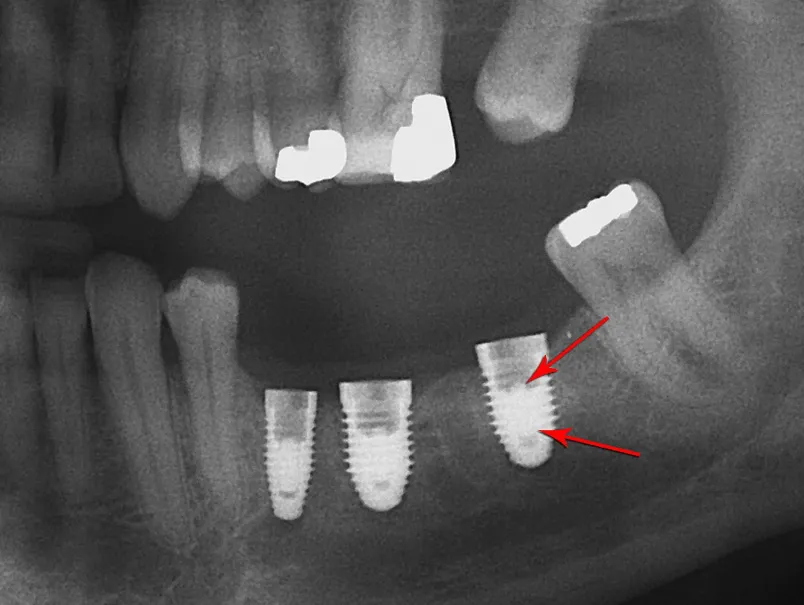

Clinical Application of a Shape Memory Implant Abutment System

A clinical study evaluating a novel shape memory implant abutment system using nitinol technology. This research compares the new system to traditional screw-retained and cement-retained prostheses, demonstrating improved retrievability, reduced complications, and enhanced patient satisfaction. Key findings include superior retention performance, elimination of screw loosening issues, and reduced peri-implantitis risk.